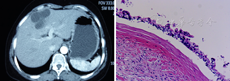

患者女,48岁。生活在牧区。因右上腹部隐痛伴乏力20天就诊。自发病以来无发热、黄疸、恶心呕吐,大小便正常。查体:腹软无压痛、肝脾未触及、肝区扣击痛(±)。实验室检查:血白细胞总数3.45×109/L,中性粒细胞45.5%。ALT 20 U/L,总胆红素8.3 μmol/L,总蛋白70.5 g/L,白蛋白39.5 g/L,ALP 64 U/L,HBSAg阴性,HCVIgG阴性。AFP 1.63 μg/L,CA-199 9.96 kU/L,CA72-4 1.82 kU/L,CEA 2.3 μg/L。包虫病血清抗体阳性(可出现假阳性)。B超肝左叶内可见数无回声团块融合,大小约7.8 cm×5 cm。可见多个强回声,后方伴弱声影。CDFI示其内血流信号不明显,提示肝内囊性肿物。CT左内叶镰状韧带旁可见不规则液性密度影,其内可见分隔多房,大小约7.8 cm×4.4 cm,周边似见条片状脂肪密度影。提示肝内囊性肿物,考虑良性(图1)。术前诊断:肝脏囊性肿物,肝包虫病?

全麻下手术探查见肝S4段有一肿物,不规则,略凸出于肝表面。经透明包膜见白色内容物,肿物外围1 cm做标记预切除线,计时阻断第一肝门,完整切除肿物,大小8.5 cm×7.5 cm。病理大体标本为灰粉囊壁样组织,大小8.5 cm×7.5 cm×3 cm,一侧壁光滑,另侧壁粗糙,可见灰黄色附着物,囊壁厚0.5~2 cm。镜下所见囊壁由纤维结缔组织及平滑肌构成,内衬假复层纤毛柱状上皮,部分内衬上皮脱失。囊壁间淋巴细胞灶状聚集,散在小胆管增生。囊壁外为少许肝组织(图2)。诊断为肝脏纤毛前肠囊肿。